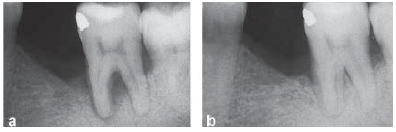

Figura 1

Aspecto radiográfico de um defeito na área de furca antes do

tratamento (a) e 6 meses após o tratamento (b).

LINDHE J, LANG NP, KARRING T. Tratado de periodontia clínica e implantologia

oral. 5. ed. Rio de Janeiro: Guanabara Koogan, 2010. p. 797.

Paciente apresenta-se com mobilidade dentária grau 2 no elemento 37. Uma área radiolúcida pode ser vista na radiografia (Fig. 1-a). À sondagem, não foi detectada bolsa periodontal na região de furca, apenas 6 mm no sítio distal e 5 mm no sítio mesial.

Nessa situação, o diagnóstico e o tratamento da lesão da área da furca são, respectivamente,